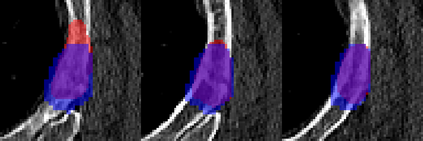

Rib fractures are a common and potentially severe injury that can be challenging and labor-intensive to detect in CT scans. While there have been efforts to address this field, the lack of large-scale annotated datasets and evaluation benchmarks has hindered the development and validation of deep learning algorithms. To address this issue, the RibFrac Challenge was introduced, providing a benchmark dataset of over 5,000 rib fractures from 660 CT scans, with voxel-level instance mask annotations and diagnosis labels for four clinical categories (buckle, nondisplaced, displaced, or segmental). The challenge includes two tracks: a detection (instance segmentation) track evaluated by an FROC-style metric and a classification track evaluated by an F1-style metric. During the MICCAI 2020 challenge period, 243 results were evaluated, and seven teams were invited to participate in the challenge summary. The analysis revealed that several top rib fracture detection solutions achieved performance comparable or even better than human experts. Nevertheless, the current rib fracture classification solutions are hardly clinically applicable, which can be an interesting area in the future. As an active benchmark and research resource, the data and online evaluation of the RibFrac Challenge are available at the challenge website. As an independent contribution, we have also extended our previous internal baseline by incorporating recent advancements in large-scale pretrained networks and point-based rib segmentation techniques. The resulting FracNet+ demonstrates competitive performance in rib fracture detection, which lays a foundation for further research and development in AI-assisted rib fracture detection and diagnosis.